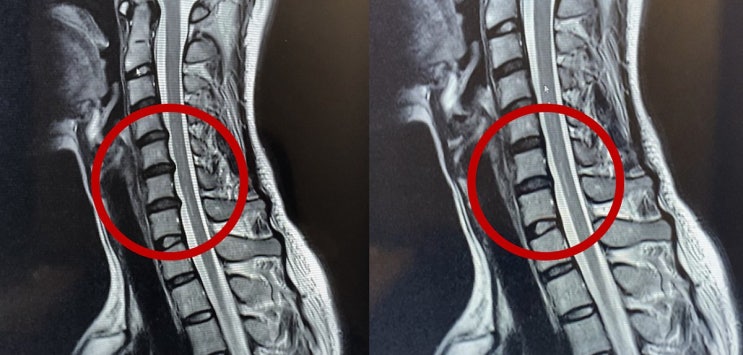

거북목 있으신분? 제발 경추베개 신중히 고르시길

거북목 5년 이상, 뒷목, 등, 어깨 통증에 두통까지... 경추 베개에만 200만원 이상 쓰고 알게 됐습니다. 사...